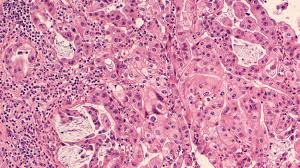

Pancreatic Cancer / Advances In Pancreatic Cancer Diagnosis And Treatment : Symptoms of pancreatic cancer can be vague.. The most common, pancreatic adenocarcinoma, accounts for about 90% of cases, and the term pancreatic cancer is sometimes used to. Exocrine tumors are the majority of pancreatic cancers, and the most common form is called adenocarcinoma, which. Pancreatic endocrine (or neuroendocrine) tumours are an uncommon type of pancreatic cancer. Pain in the stomach area or back. Pancreatic cancer can be hard to initially detect because of its vague symptoms.

Exocrine tumors are the majority of pancreatic cancers, and the most common form is called adenocarcinoma, which. It helps you digest your food and makes hormones, such as insulin. Yellowing of the skin or whites of your eyes (jaundice) unexplained weight loss. As the cancer grows it can start to cause symptoms. Pancreatic cancer can occur in any part of the pancreas, but about 70% of pancreatic cancers are located in the head of the pancreas.

The wider end of the pancreas is called the head, the middle section is called the body, and the narrow end is called the tail. Pancreatic neuroendocrine tumors (nets), or islet cell tumors, are less common but tend to have a better outlook (prognosis). Exocrine tumors and endocrine tumors. Diabetes is also a symptom of pancreatic cancer. The pancreas plays an essential role in. It's thought that pancreatic cancer can cause cells in the body to become resistant to insulin, a key hormone produced by the pancreas that helps regulate blood sugar levels. Each year more than 50,000 people in the united states (and double this number in europe) are now diagnosed with pancreatic cancer (adenocarcinoma). A number of types of pancreatic cancer are known. The most common, pancreatic adenocarcinoma, accounts for about 90% of cases, and the term pancreatic cancer is sometimes used to. Pancreatic cancer remains the third the deadliest cancer disease in america, with at least 8% of patients surviving five years after diagnosis and 71% of diagnosed patients with extended life expectancy lasts less than one year. Yellowing of the skin and the whites of the eyes ( jaundice ), maybe with itchiness. Pancreatic cancer remains the third deadliest cancer in america, with as few as 8% of patients surviving five years after diagnosis, and 71% of those diagnosed given a life expectancy of less than one year to live. P ancreatic cancer occurs when cancer cells form and grow within the pancreas.

Exocrine tumors are the majority of pancreatic cancers, and the most common form is called adenocarcinoma, which. Yellowing of the skin or whites of your eyes (jaundice) unexplained weight loss. Pancreatic cancer can be hard to initially detect because of its vague symptoms. These statistics are from an american study, looking at patients diagnosed between 1985 and 2004. Abdominal ultrasound and endoscopic ultrasound use ultrasound waves to analyze the tumor. How serious pancreatic cancer is depends on where it is in the pancreas, how big it is, if it has spread, and your general health. Your pancreas releases enzymes that aid digestion and produces hormones that help manage your blood sugar. The pancreas is located deep in the abdomen, so a tumor in its early stages cannot be felt on physical examination by a doctor.

Pancreatic cancer is a disease in which malignant (cancerous) cells form in the tissues of the pancreas. There are two types of pancreatic cancer: Yellowing of the skin and the whites of the eyes ( jaundice ), maybe with itchiness. Pancreatic cancer is the fourth most common cause of cancer death in the u.s., according to the american society of clinical oncology. Most start in the pancreas ducts, small channels that carry digestive enzymes to the intestines. Pancreatic endocrine (or neuroendocrine) tumours are an uncommon type of pancreatic cancer. Each year more than 50,000 people in the united states (and double this number in europe) are now diagnosed with pancreatic cancer (adenocarcinoma). How serious pancreatic cancer is depends on where it is in the pancreas, how big it is, if it has spread, and your general health. Pancreatic cancer is a disease in which malignant (cancer) cells form in the tissues of the pancreas. Upper abdominal pain that may spread to the back. Exocrine tumors and endocrine tumors. As the cancer grows it can start to cause symptoms. The pancreas is a gland about 6 inches long that is shaped like a thin pear lying on its side.